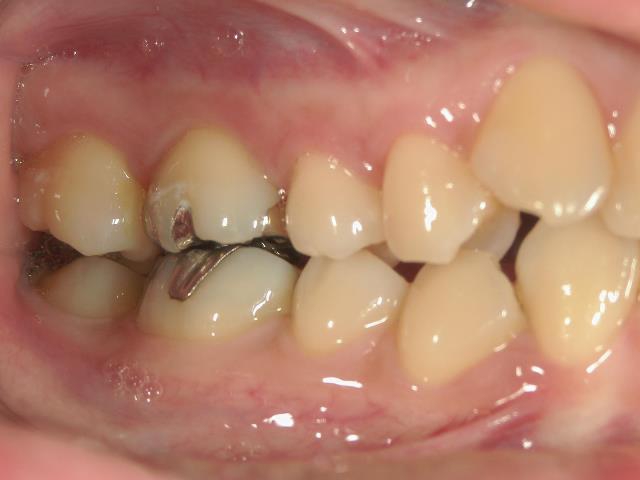

矯正歯科 治療前